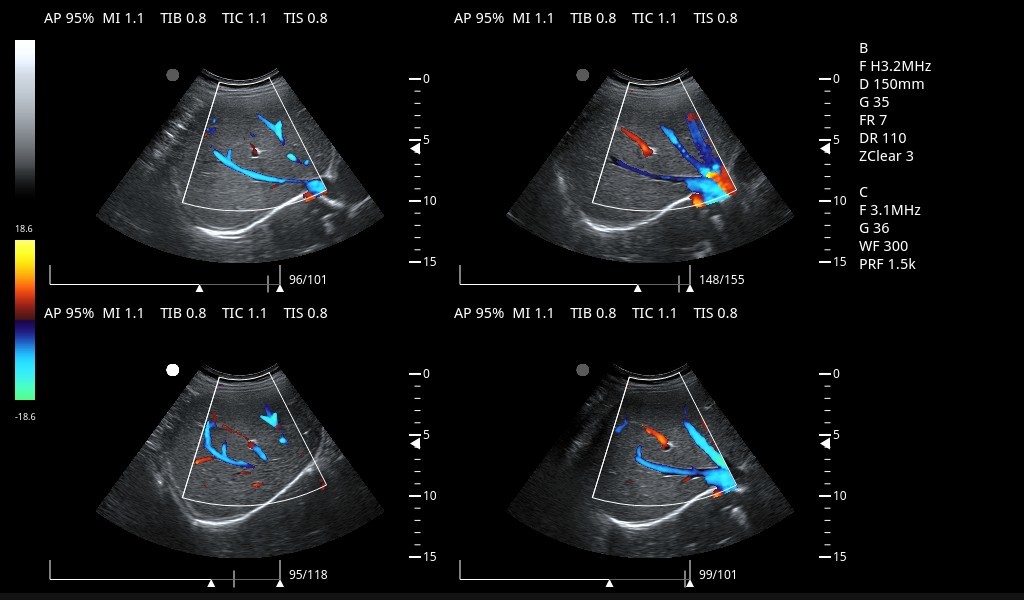

Excelentes imágenes clínicas

|

|

|

|

|

|